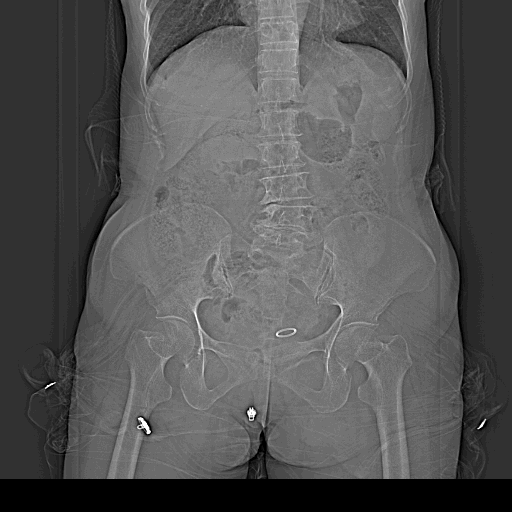

CT53730:患者,女,65岁,突发腹痛2小时

患者,女,65岁,突发腹痛2小时

肝左叶可见多个类圆形低密度影,边缘光整,腹壁稍膨隆,膀胱上方及右中上腹脐旁可见团状袋状软组织密度肿块大部分被肠管包绕且部分与肠管影相连。子宫内见环状钙化,双侧附件区点状钙化。考虑:腹内疝-----十二指肠旁疝?膀胱上疝?子宫肌瘤钙化可能。肝囊肿。必要时增强或MRI检查。

右侧十二指肠旁疝。

腹内疝(十二指肠旁疝)伴绞窄性肠梗阻(缆绳征)可能。

肠扭转【增大窗宽】